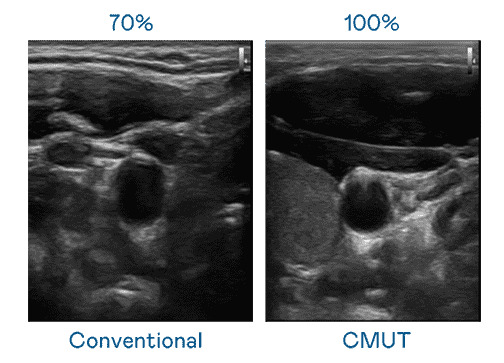

CMUT 技术是一种用电容式微机电元件来产生超音波讯号的技术。。与传统 PZT 压电式技术相比,,CMUT 频宽增加 30%,,,,更宽频的超音波讯号让影像解析度大幅提升,,,是实现高影像品质医疗超音波扫描、、、促进精准医疗发展的关键技术。。。。

大频宽带来超清晰影像

超音波影像的解析度高低,,,首先取决于探头能发出的讯号频宽。。。。人生就是博 CMUT 可提供高清晰的超音波讯号,,,,提供高频宽、、、、高灵敏度、、、、影像纹理细节更高的超音波影像,,协助医护人员缩短影像判读时间及利用精准的医疗影像进行诊断。。。